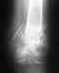

Закрытый оскольчатый двухлодыжный перелом правой голени со смещением, наружный вывих стопы.Закрытый многооскольчатый перелом дистального метаэпифиза костей левой голени со смещением, подвывих стопы к снаружи.

Упала с 5 этажа.Получила:Закрытый оскольчатый двухлодыжный перелом правой голени со смещением, наружный вывих стопы.Закрытый многооскольчатый перелом дистального метаэпифиза костей левой голени со смещением, подвывих стопы к снаружи. Проводилась закрытая репозиция,скелетное вытяжение, остеосинтез обеих голеней,заживление первичное,иммобилизация циркулярная.Достаточно ли это лечение?Врачебные рекомендации?